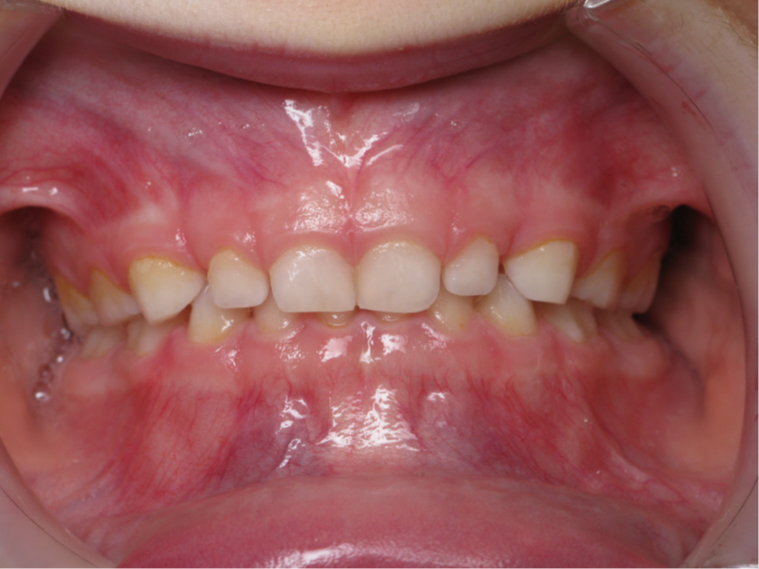

4.supraclusion inversé gauche 4 ans

inversion des dents postérieur coté gauche

bilan début et fin de traitement